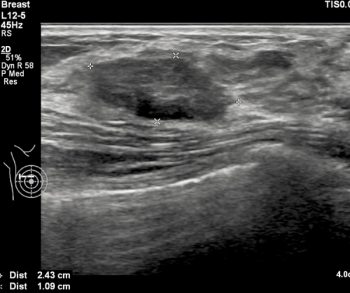

In order to facilitate optimal detection and assessment of liver fibrosis and steatosis, the newly launched Hepatus 6 Diagnostic Ultrasound System offers the capabilities of real-time two-dimensional ultrasound with visual transient elastography in one device.